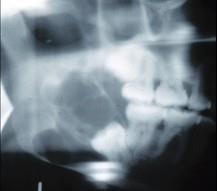

女,32岁,右下后牙龈向外膨隆,后牙渐松动3个月。X线片(如图)示右下颌磨牙区颌骨呈蜂房样改变,病变区牙根呈锯齿状吸收。该病人最可能的诊断是 ( ...

选项 A.右下颌骨骨肉瘤 B.右下颌骨角化囊肿 C.右下颌骨成釉细胞瘤 D.右下颌骨骨巨细胞瘤 E.右下颌骨中央性颌骨癌

答案 C